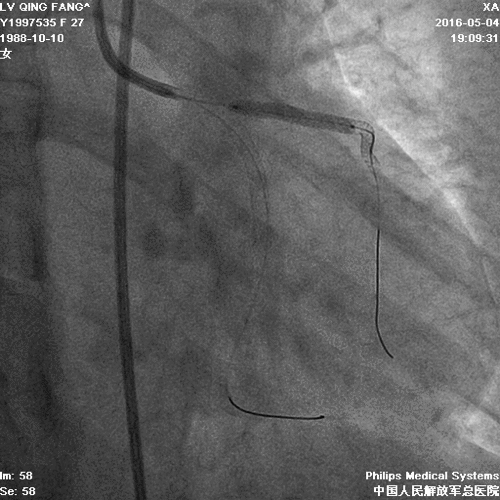

PCI